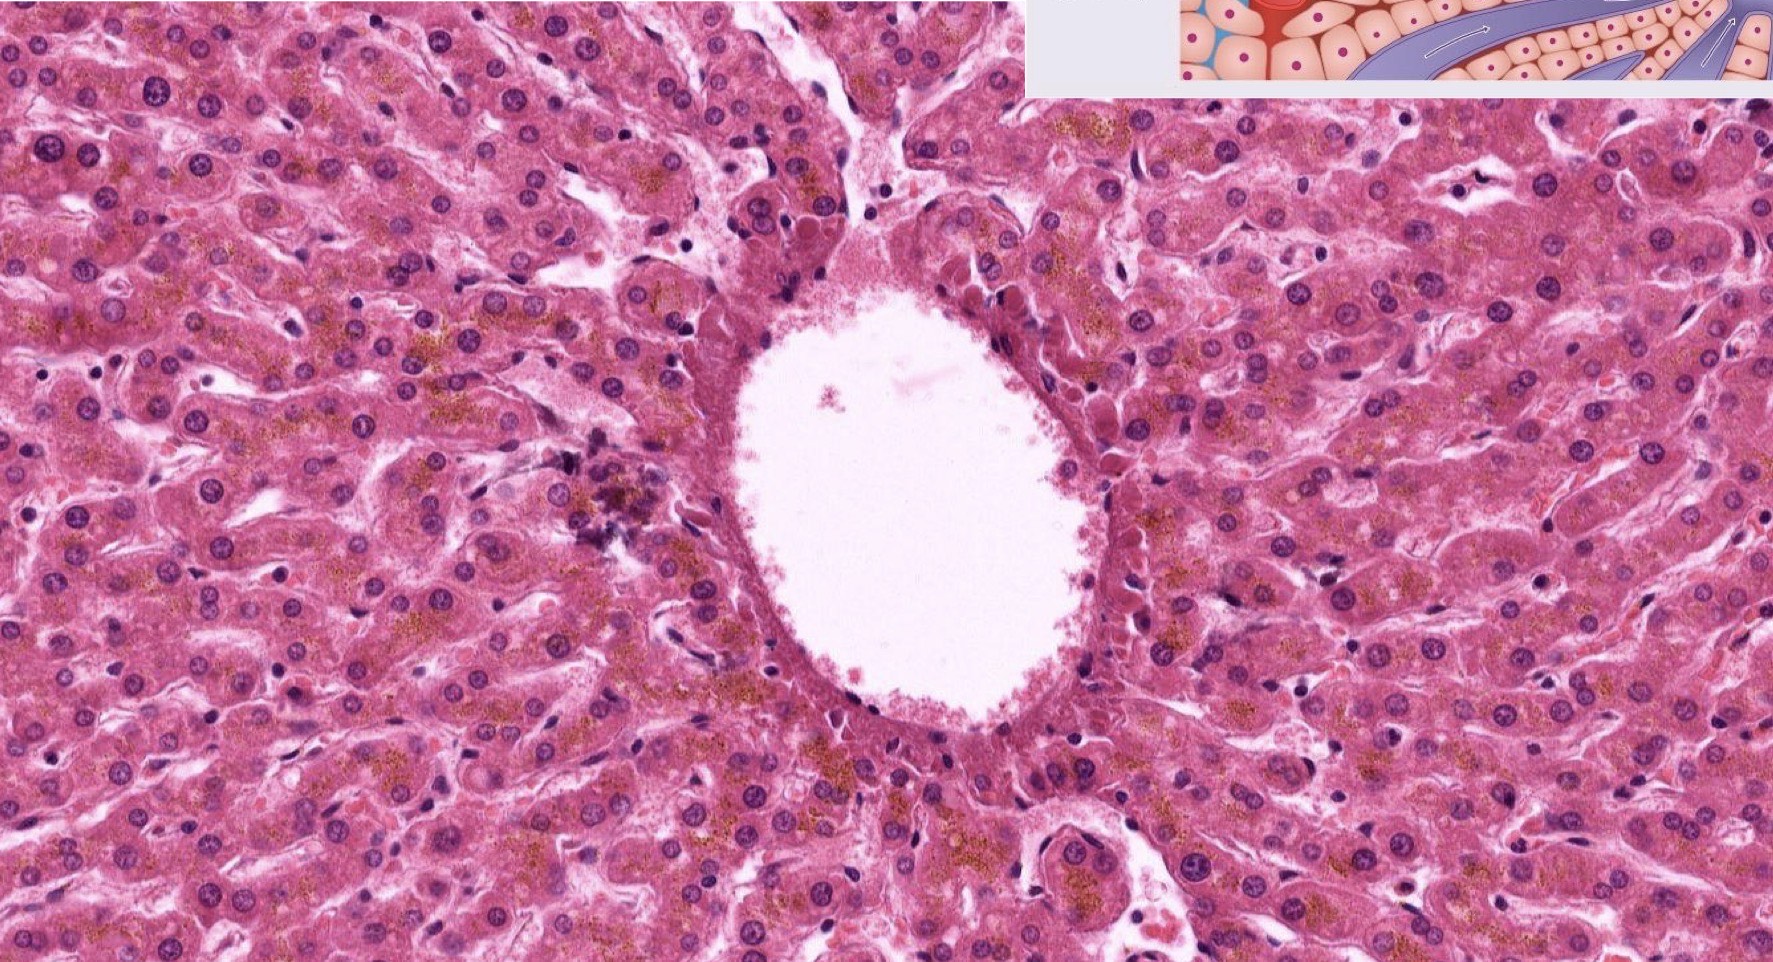

Identify the Organ and Structures?

Liver; Central vein, surr by Hepato and Sinu

Liver; Hepatocytes (polyploidy)

Liver; Hepatocytes, some being binucleate which is common